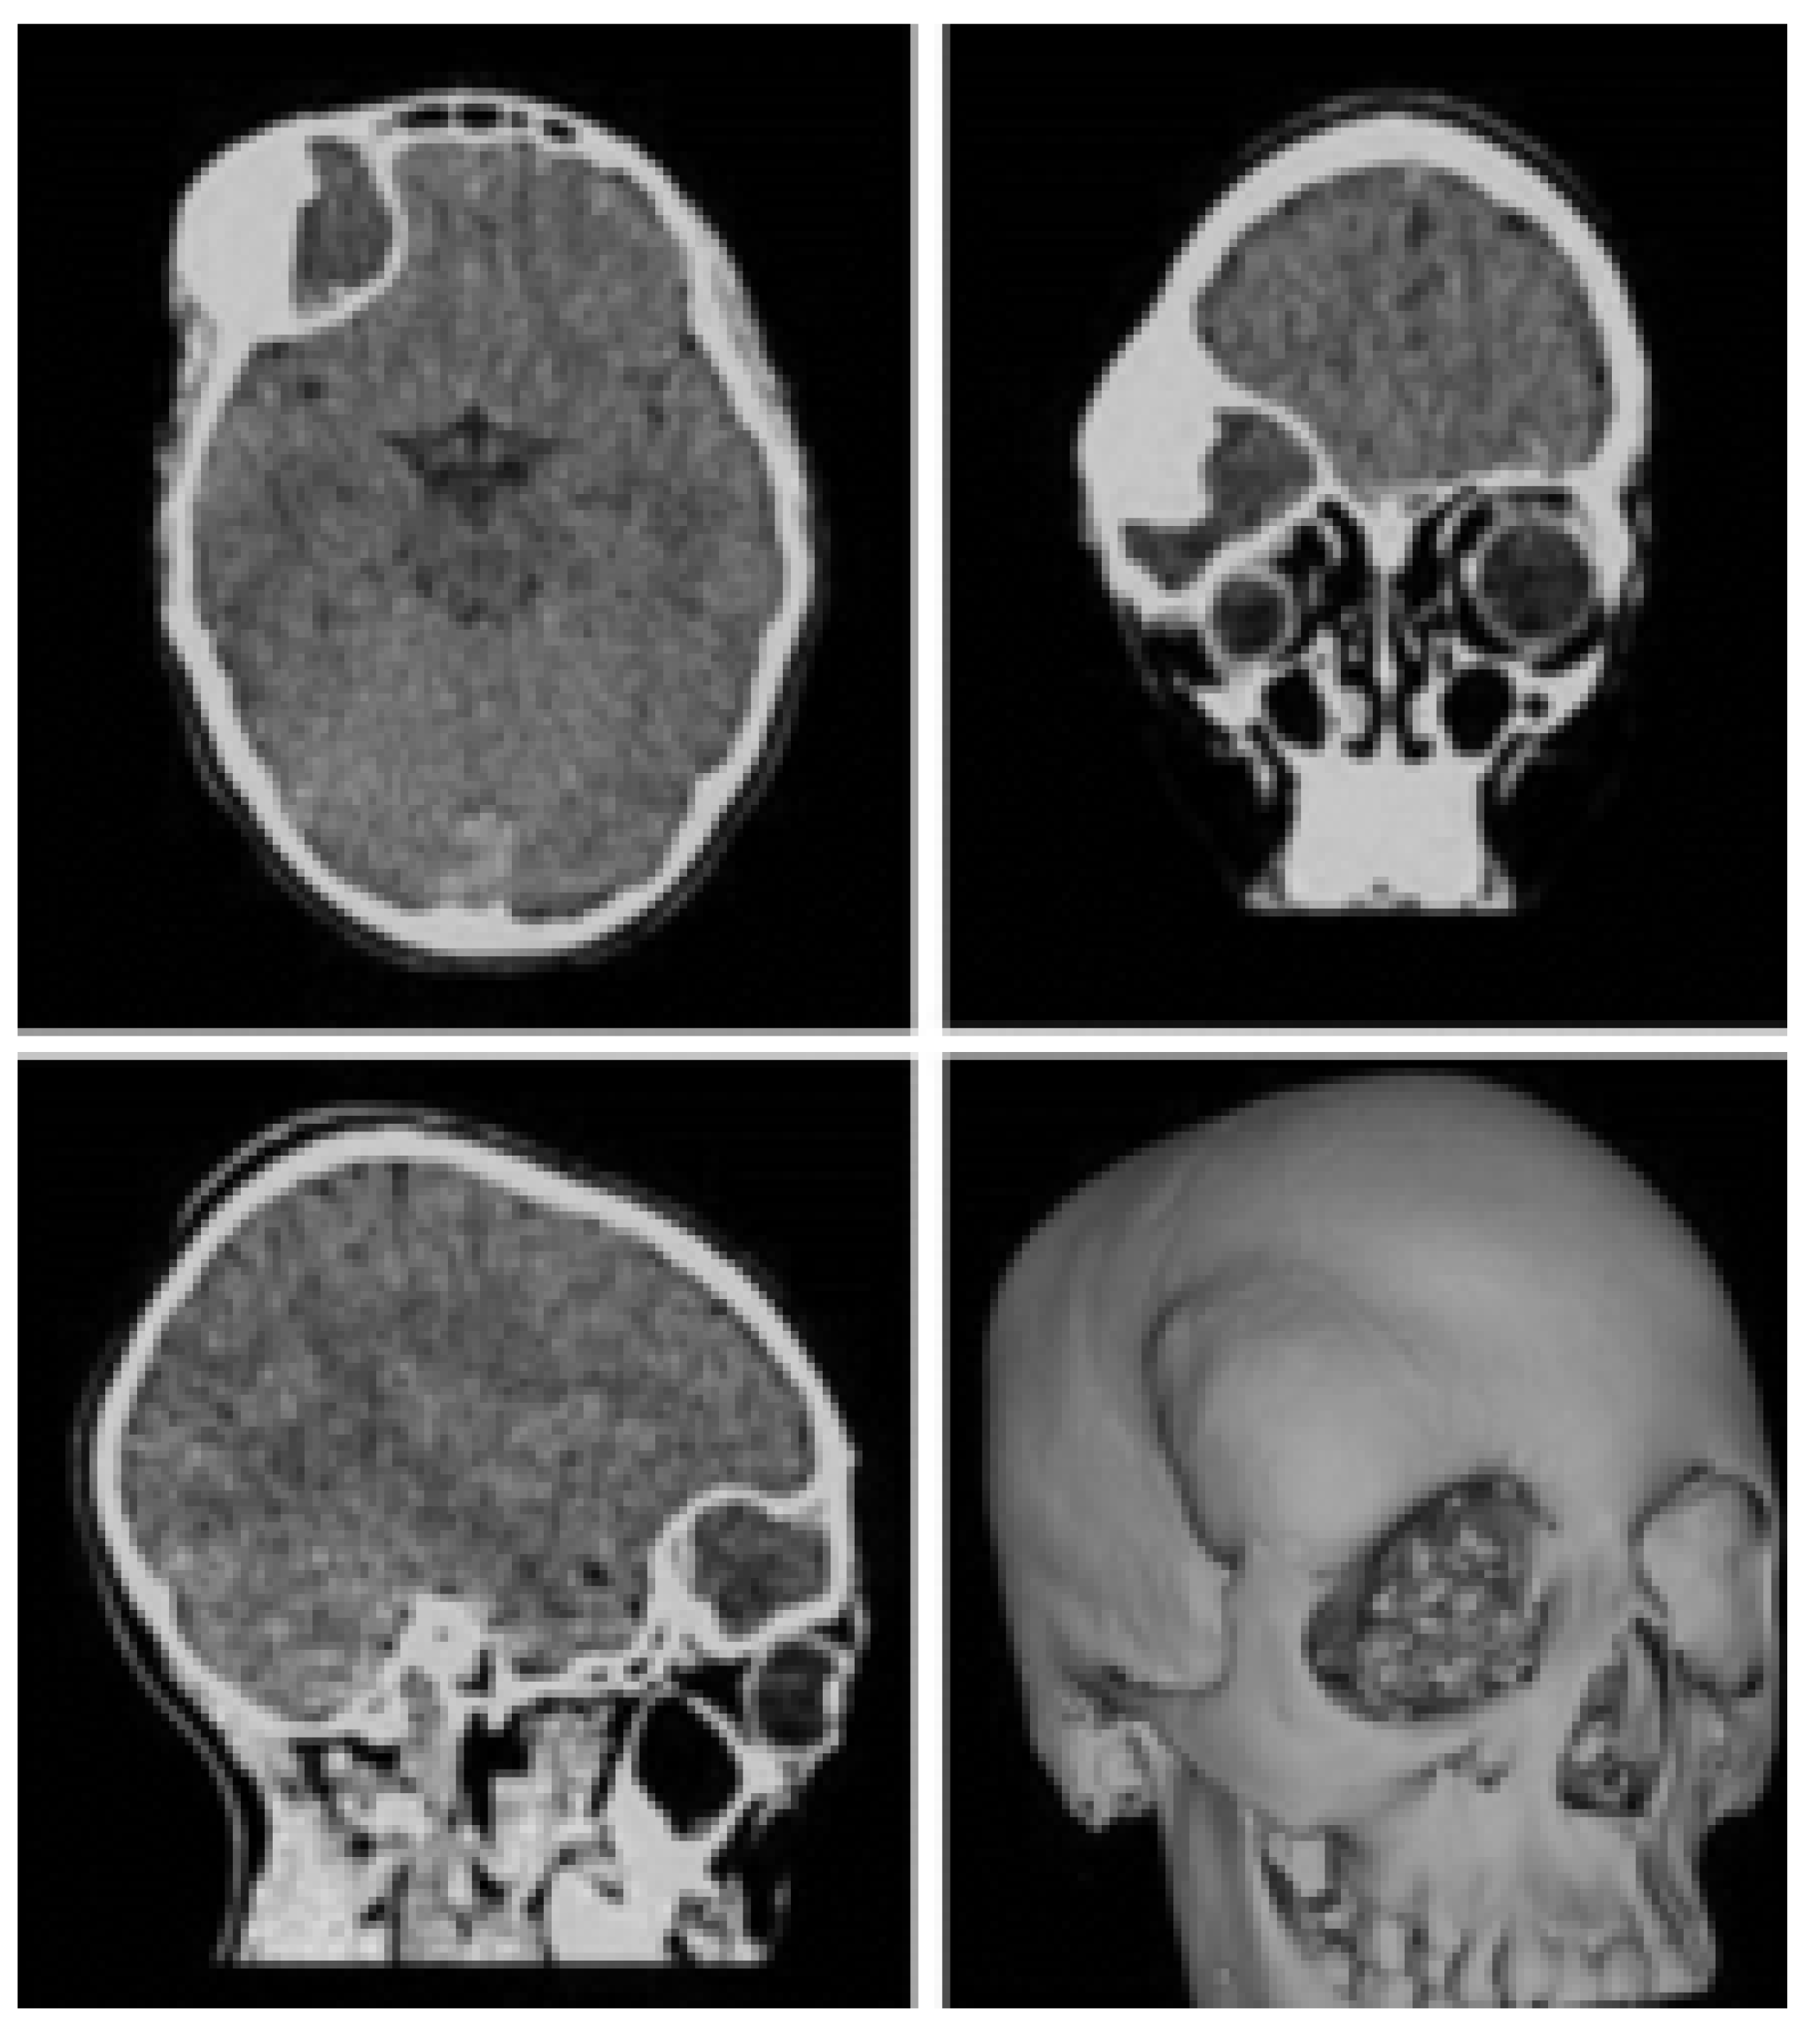

3.3. Case 3: Osteofibrous Dysplasia

3.3.1. Diagnosis and Analysis

3.3.2. Surgical Planning

3.3.3. Planning and Printing Anatomical Models